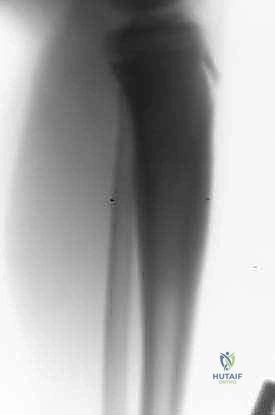

المرحلة الخامسة: التثبيت والإغلاق (Fixation and Closure)

يتم تثبيت الشظية المزروعة بقوة مع نهايات العظم الأصلي باستخدام شرائح معدنية ومسامير أو مثبتات خارجية. يضمن هذا التثبيت الميكانيكي استقرار العظم حتى يكتمل الالتئام البيولوجي.

- بناءً على صور الأشعة السينية التي تؤكد بدء التئام العظم المنقول مع العظم الأصلي، يسمح الأستاذ الدكتور هطيف بالتحميل الجزئي التدريجي باستخدام العكازات.

- العظم المنقول (الشظية) يبدأ في التضخم (Hypertrophy) استجابة للوزن المحمل عليه، ليصبح تدريجياً في سماكة وقوة العظم الأصلي المفقود.